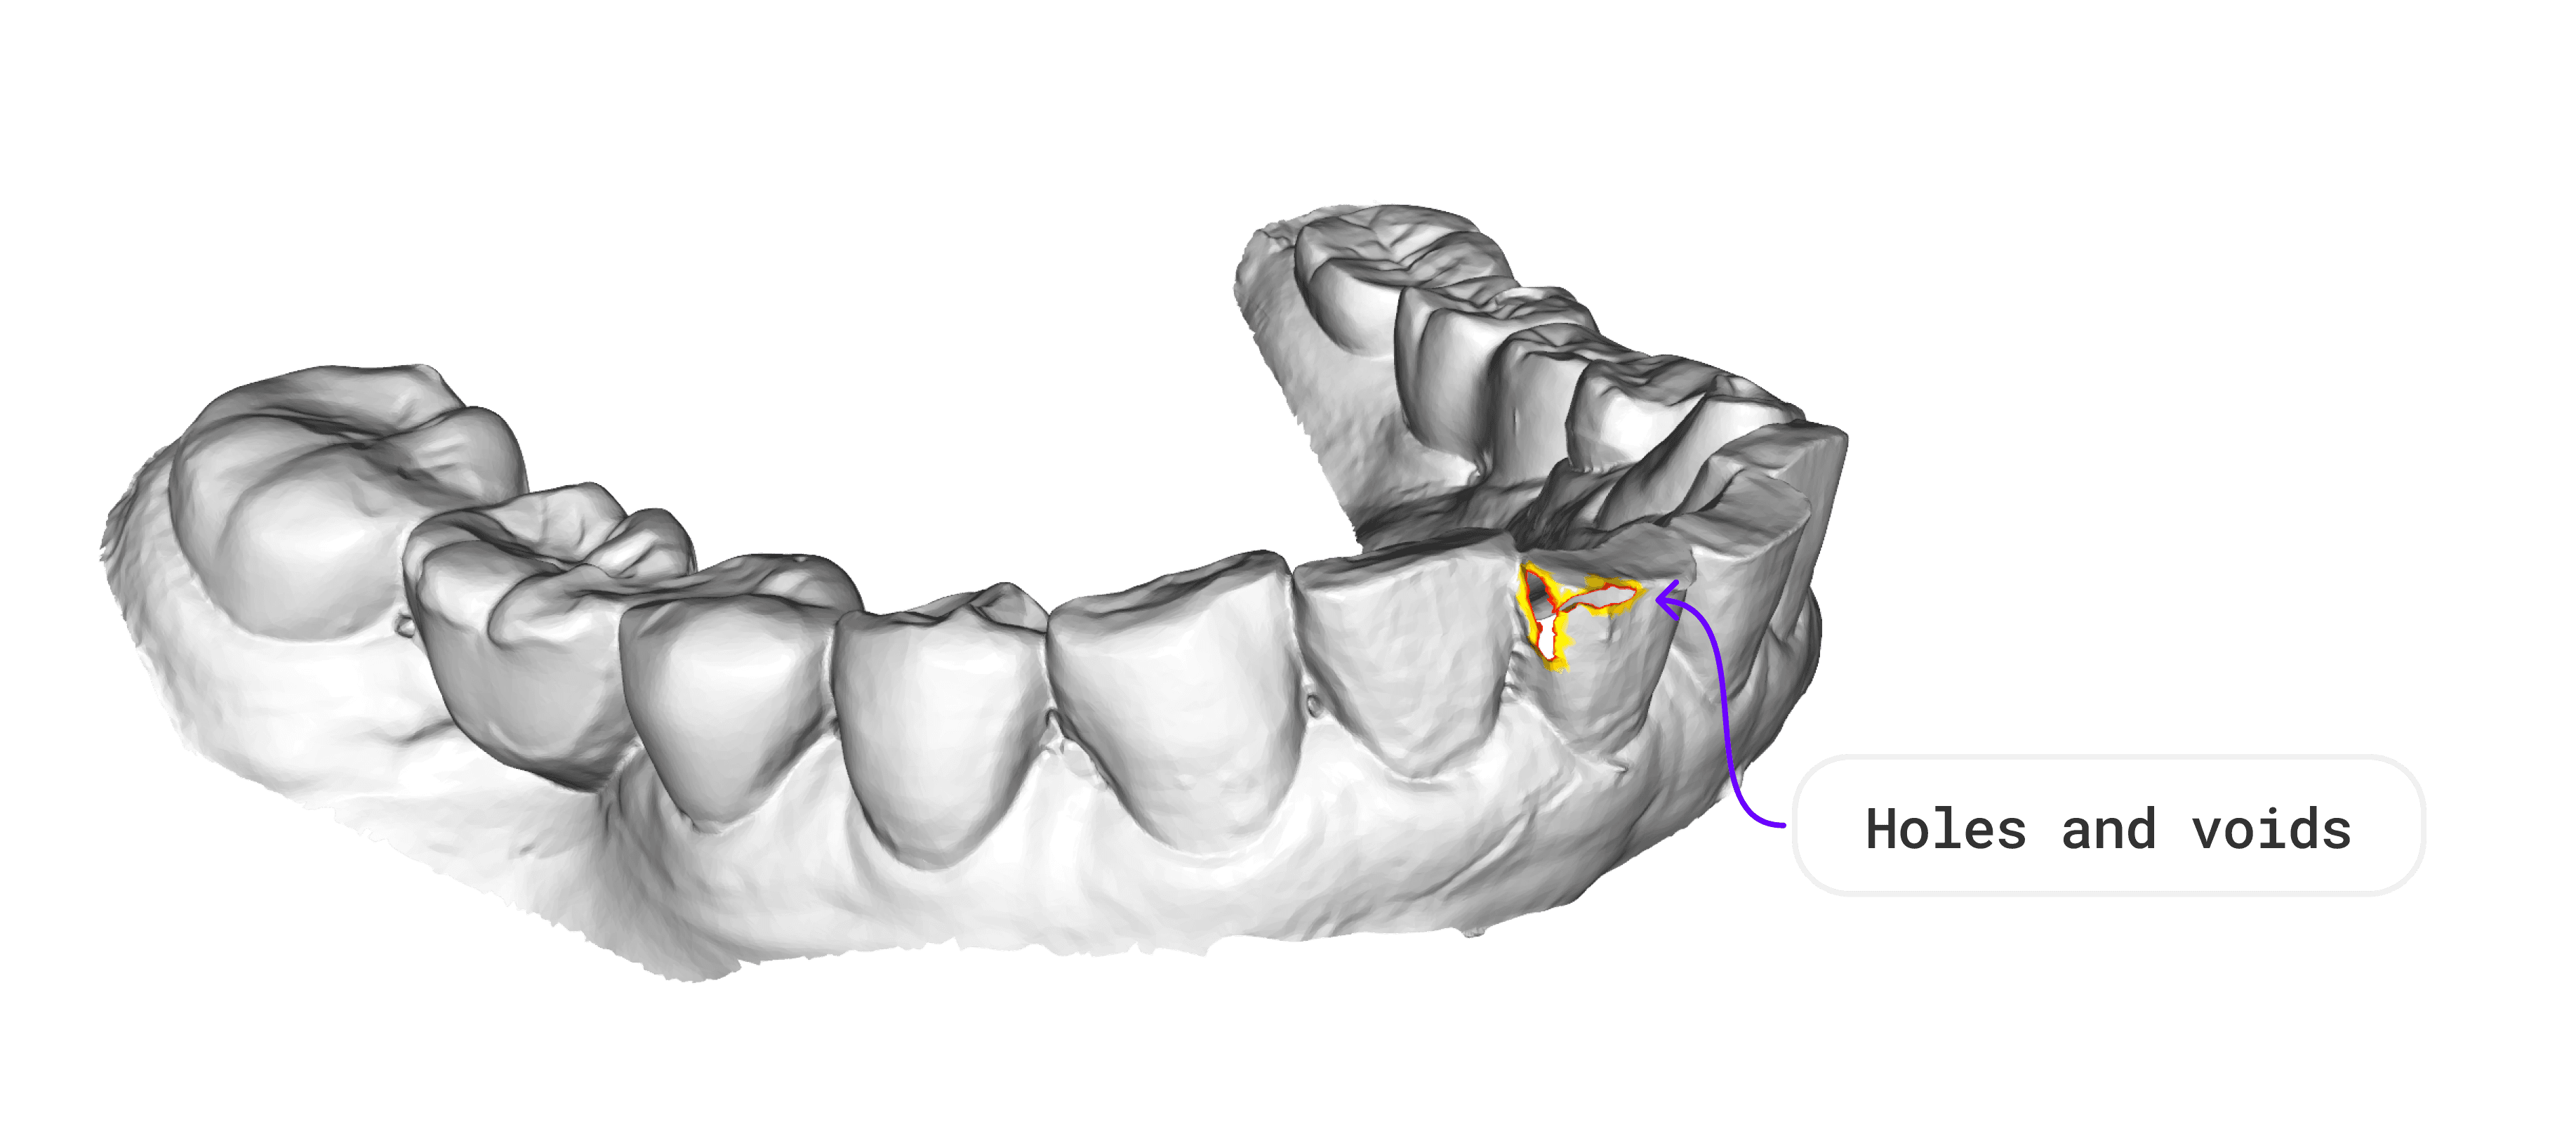

Dedicated team with proven expertise in medical image segmentation, 3D mesh processing, and computer vision for dental applications.